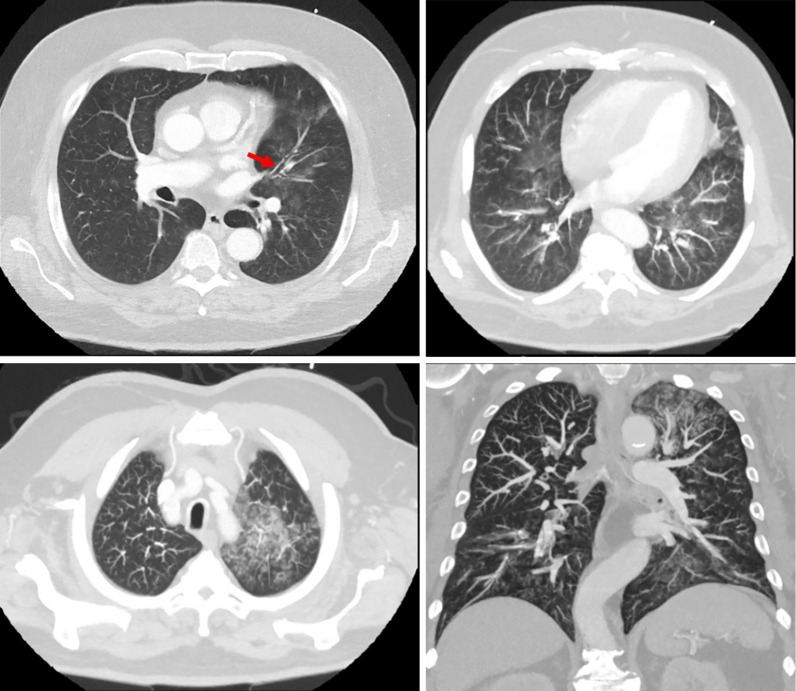

Case description: A 60-year-old obese male with no significant history of lung or cardiac disease presented to the emergency department with sudden-onset dyspnea, severe hemoptysis, palpitations, and tachycardia. Vital signs indicated hypertension (180/110 mmHg) and hypoxia [peripheral capillary oxygen saturation (SpO2) of 80% on room air]. The electrocardiogram (ECG) revealed sinus tachycardia but no right bundle branch block (RBBB). Laboratory tests were mostly unremarkable, and a computed tomography (CT) scan ruled out pulmonary embolism but showed diffuse bronchial wall thickening consistent with bronchitis or atypical pneumonia. During the clinical interview, the patient admitted to recent use of inhaled cocaine and amphetamines, leading to the diagnosis of early-stage "crack lung". After stabilization by administration of oxygen, bronchodilatators and prednisolone, the patient was discharged with follow-up care focusing on cessation of drug use and monitoring for potential lung damage. Bronchoscopically, there was no evidence of another cause of hemorrhage such as tumor growth.